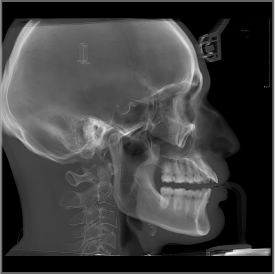

单圈扫描可同时获得CT、3D全景及3D正侧位影像,患者无需多次摆位。

视野最大可至24×21cm,即使对于体型偏胖、脸型较大的患者,也都游刃有余。多种视野范围可供临床选择:24×21cm、16×13cm、5×5cm。

24×21的视野,可以完全覆盖患者上至额顶、下至颈角部位,前至鼻尖的范围